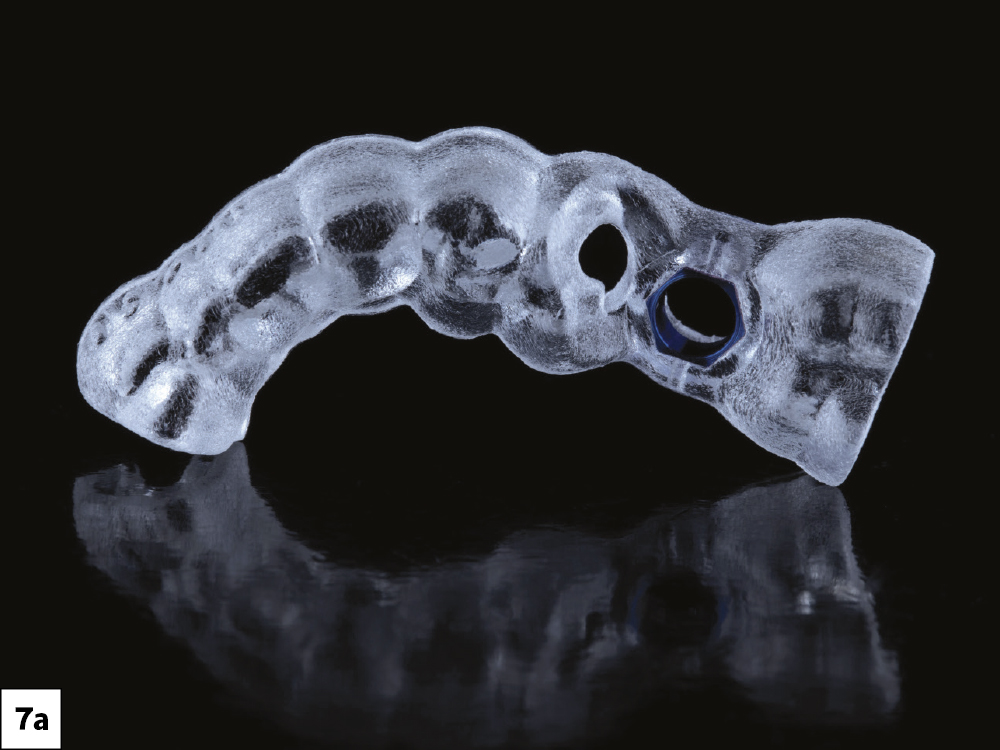

Figures 7a–7c: For this procedure, I selected a custom Glidewell™ Tooth Replacement Solution bundle, which included a tooth-supported surgical guide, the implant, a custom healing abutment, a scan body, and the final screw-retained restoration. I also used the Glidewell HT Implant Guided Surgical Kit (Glidewell Direct).